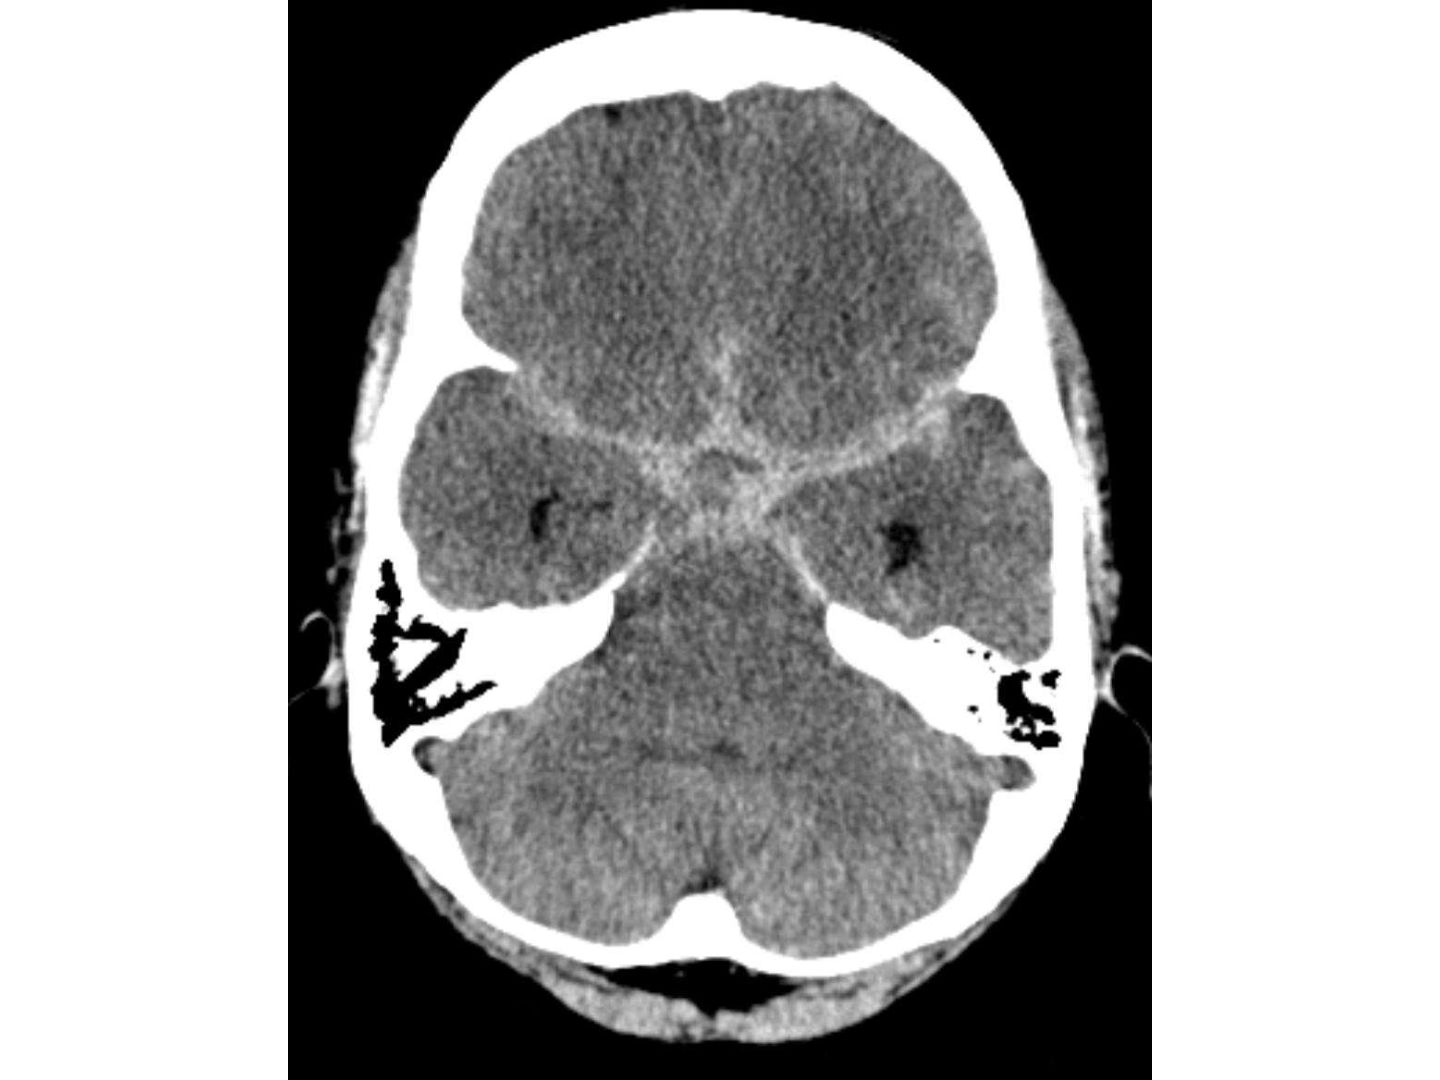

Computertomografische Aufnahme einer subarachnoidalen Blutung (SAB) mit sternförmig hyperdensen Blutansammlungen in den basalen Zisternen. Diese entstehen typischerweise nach dem Riss eines Aneurysmas einer großen Hirnarterie, wodurch Blut in den Liquorraum austritt. Klinisch führt dies zu plötzlichen, extremen Kopfschmerzen („Donnerschlagkopfschmerz“) und akuter Lebensgefahr.

CTT: Subarachnoidale Blutung - Computertomografische Aufnahme einer subarachnoidalen Blutung (SAB) mit sternförmig hyperdensen Blutansammlungen in den basalen Zisternen. Diese entstehen typischerweise nach dem Riss eines Aneurysmas einer großen Hirnarterie, wodurch Blut in den Liquorraum austritt. Klinisch führt dies zu plötzlichen, extremen Kopfschmerzen („Donnerschlagkopfschmerz“) und akuter Lebensgefahr.

Hellerhoff. (2010, 21. Januar). Subarachnoidale Blutung in der Computertomographie – hyperdenses Blut in den basalen Zisternen (sternförmige Aufhellung in der Mitte). Wikimedia Commons. https://commons.wikimedia.org/wiki/File:SAB_basal_bei_Aneurysma.jpg

CC BY-SA 3.0